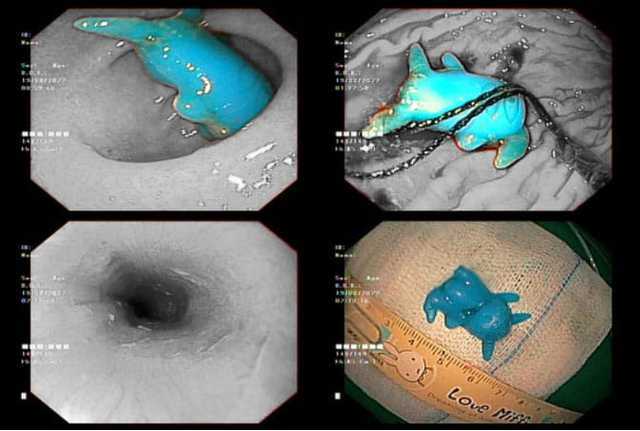

Pikachu đồ chơi kẹt trong thực quản bé 6 tuổi Sau khi ngậm đồ chơi pikachu và nuốt vào bụng, trẻ than đau ngực nên gia đình đưa đi cấp cứu.